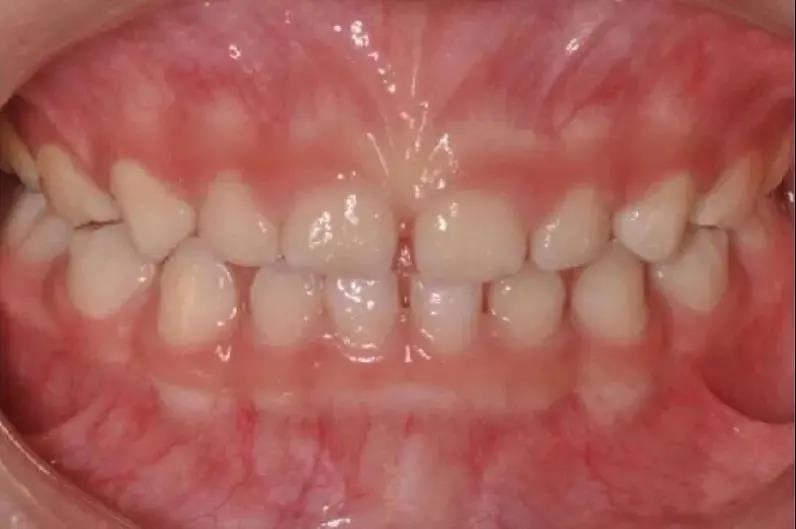

如發(fā)現(xiàn)孩子上下頜骨位置不佳

比如有明顯“齙牙”,應盡早矯治

錯合畸形不僅影響孩子的口腔健康

還會影響面容,

進而影響孩子的心理健康。

早期矯治可以充分利用兒童的頜骨發(fā)育潛能

調整頜骨的生長平衡及牙弓發(fā)育

因此齙牙還是要盡早診治哦